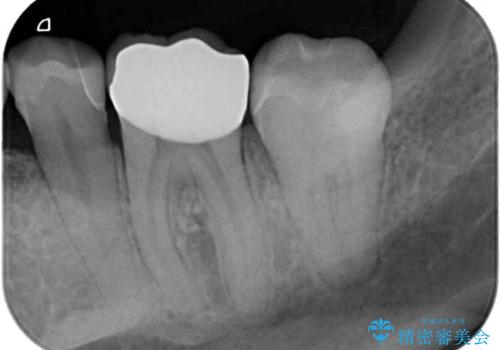

奥歯には目立つ銀歯が多くあるので、矯正治療後には下顎の銀歯をセラミッククラウンやセラミックインレーにより、補綴・修復治療することとしました。